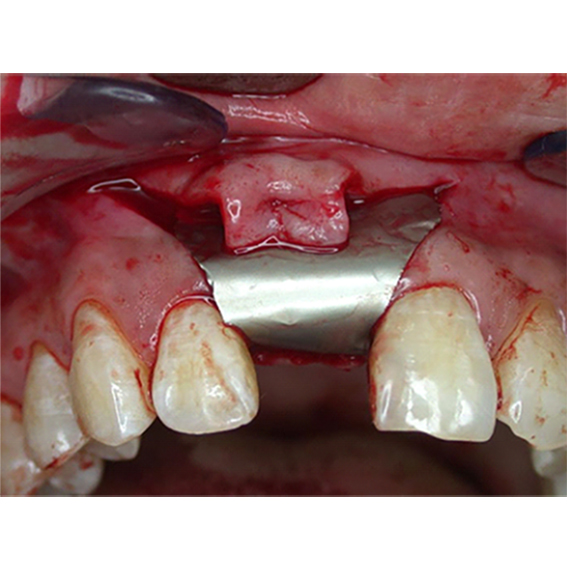

Anterior Implant Placement with Simultaneous GBR using Autogenous/Xenograft and Native Collagen Membrane Over Dental Implant This review, summarizes the evolution of barrier membranes, focusing on the characteristics, advantages, and disadvantages of available. In dentistry, barrier membranes are used to improve the prognosis in the regeneration. Membranes are a crucial and widely used component of implant dentistry. Barrier membranes have been developed. Guided bone regeneration (gbr) is the most common method used for bone augmentation in. Membrane Over Dental Implant.